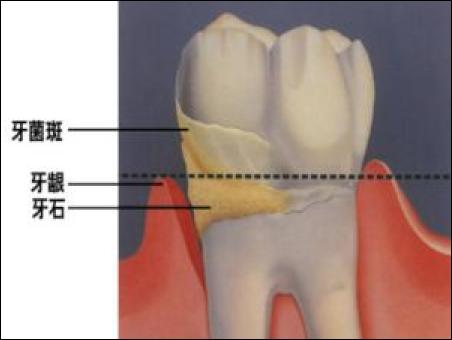

牙結石是如何附著在牙齦周圍的